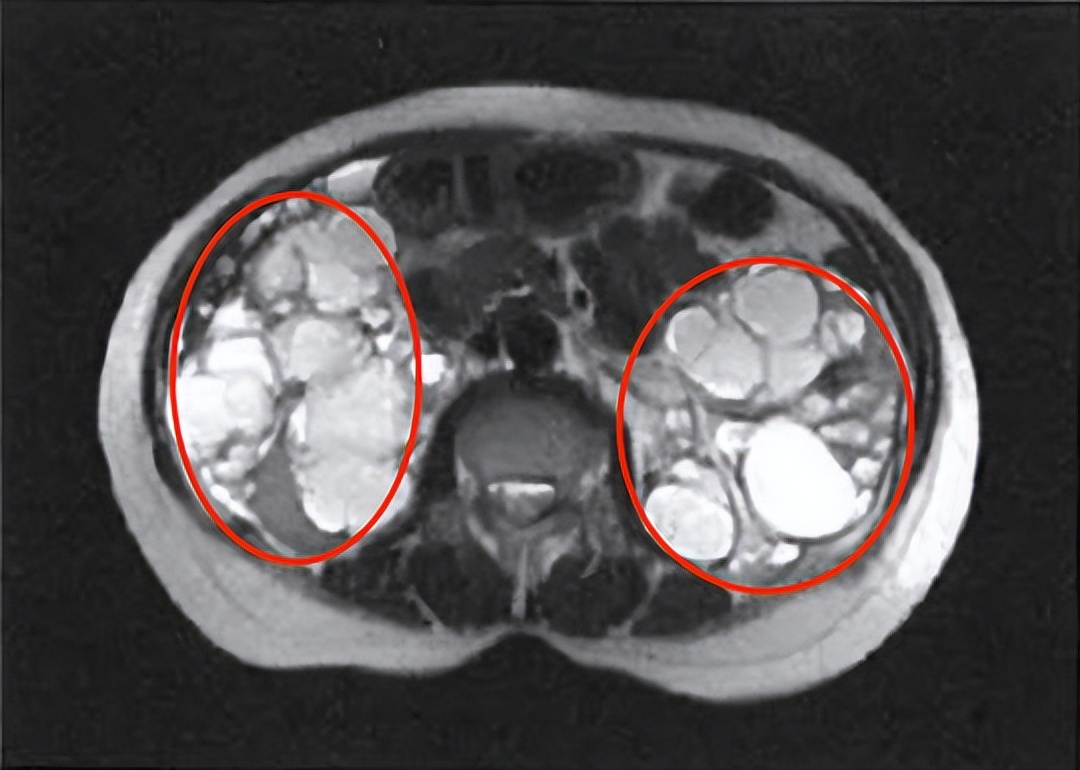

MRI显示下的多囊肾☝